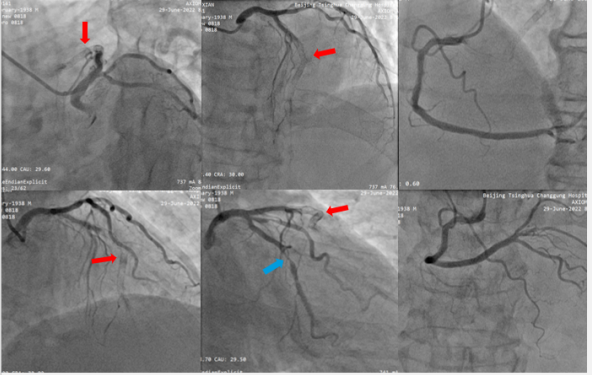

LAD介入治疗过程:首先在Finecross微导管支撑下尝试Fielder XT导丝不能通过病变,更换Gaia 2导丝,通过病变后,使用2.0*20mm球囊预扩后行OCT评估。发现支架内弥漫性再狭窄,最小支架内管腔面积(MSA) 0.88mm²,狭窄处可见双层金属支架影,增生斑块为环形钙化病变。(如图4

图4:LAD 预扩张后OCT检查

首先行LAD 准分子激光斑块消蚀术(ELCA)。选择1.4mm激光导管。能量最大选择60mJ/mm²,频率50Hz。并使用造影剂灌注爆破技术等,支架内膜下钙化斑块虽然有变化,但整体形态没有太大改变。随后使用3.0*15mm NC 耐高压球囊进行扩张,最大压力达到26atm,狭窄病变处仍然不能被有效扩张(图5)。

图5:准分子激光斑块消蚀术